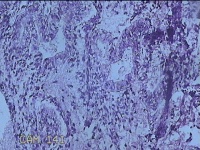

子宫腔内容物

性别

女

年龄

33岁

临床诊断

子宫内膜息肉?子宫异常出血

一般病史

阴道流血12天。

标本名称

大体所见

;纱布一块,内有灰白暗红色不规则碎组织3.5x2.8x1.3cm一堆。